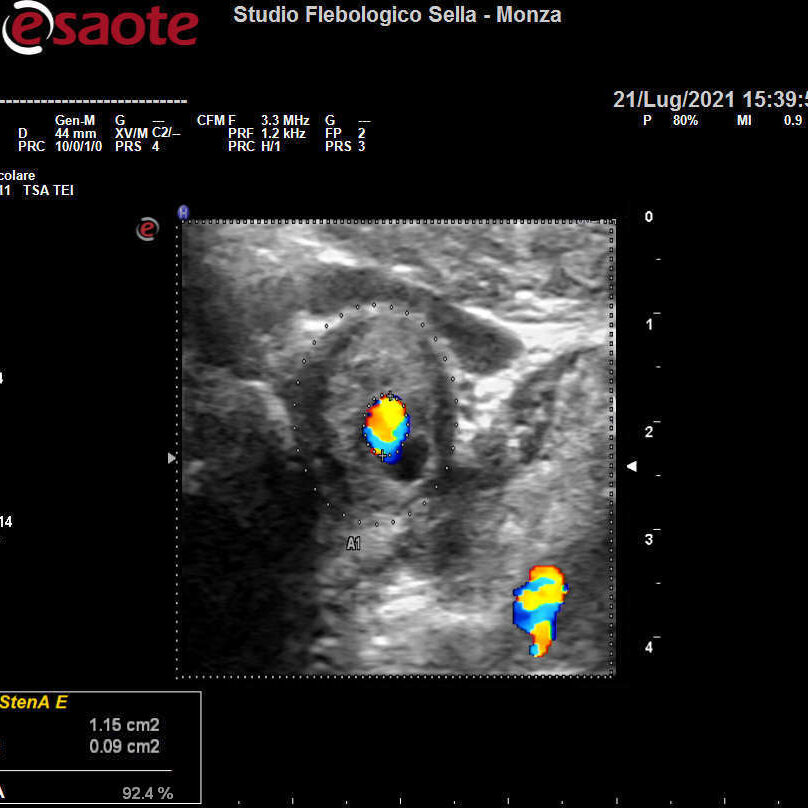

Abbiamo precedentemente visto come l’intuizione del fisico austriaco Christian Doppler ha posto le basi teoriche per la nascita dell’EcocolorDoppler. La deformazione degli ultrasuoni nell’attraversare il corpo umano consente la ricostruzione in immagini dei tessuti, vasi compresi. Otteniamo quindi informazioni sulla forma e il decorso dei distretti vascolari esplorati e sulla velocità del sangue contenuto. Un utile campo applicativo è rappresentato dall’EcocolorDoppler dei tronchi sovraortici ossia lo studio delle arterie del collo. Il precoce riscontro di problemi a carico di carotidi e vertebrali ne previene infatti una grave complicanza: l’ictus ischemico.